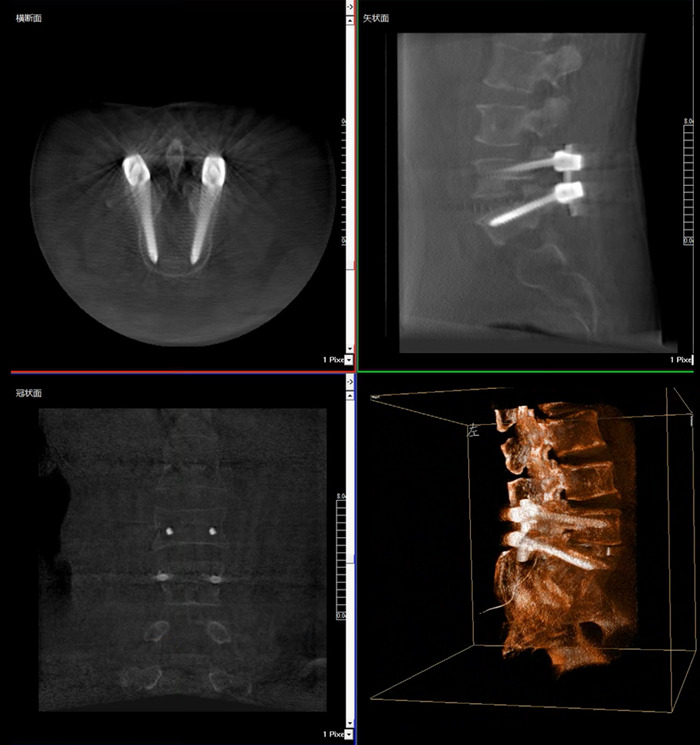

移動式三維C形臂,又稱骨科三維C臂,就是將傳統二維與“類CT模式”相結合的升級版C形臂,能在術中快速地生成橫斷面、矢狀面、冠狀面斷層圖像和三維立體圖像。通過不同方位的斷層圖像,能夠更清晰、完整地顯示椎體及其附件的解剖學結果,直觀地分析病變與周圍組織的立體空間關系,三維斷層成像能夠使手術模擬和手術方案的制定更加準確。

在MPR圖像中,冠狀面、矢狀面和橫斷面的信息大大提高了醫生對于病灶區以及手術效果的判定。

術中實時三維影像帶來的更加豐富的信息,可以作為醫生手術執行的判斷基礎,以及手術操作后實時的影像判斷依據,從而保障手術效果。

近年來,機器人導航設備在臨床的應用越來越廣泛,而三維影像是機器人導航系統手術執行的基礎,具有地圖定位和效果檢驗的雙重作用,使手術執行更加準確,手術效果驗證更有保障。